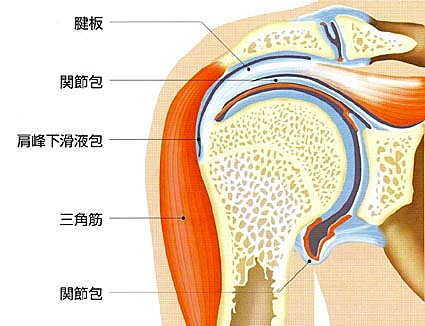

超音波診断①(正常肩関節)

肩の周りには最も重要な腱板という太い靱帯様組織、三角筋・棘上筋・棘下筋・肩甲下筋・上腕二頭筋腱・肩峰下滑液包などが見えます。